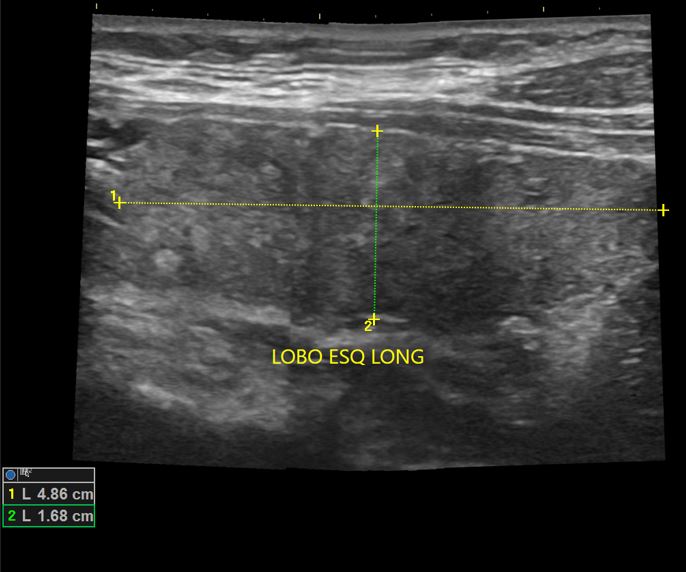

Tireoidite de Hashimoto

USG de Tireoide